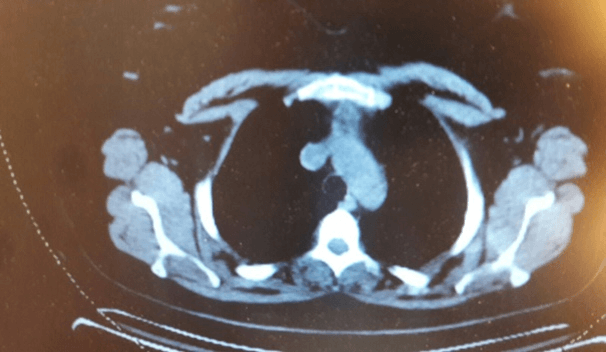

Baseline CT scan (post adjuvant chemotherapy): 1.5 cm anterior mediastinal mass; CT scan: 6 cm anterior mediastinal mass (Figures 1 & 2); PET scan: Showed no uptake in the thymus; CBC with differential showed no abnormalities or atypical lymphocytosis prior or to and after the development of thymic mass; Physical examination: No clinical signs or symptoms of myasthenia Gravis.

Figure 2: CT scan shows the anterior mediastinal mass.

The patient is a 39-year-old gravida 3 P2102 woman who had undergone total abdominal hysterectomy with bilateral salpingo-oophorectomy for stage 1C2 (T1C2-N0-M0) according to FIGO and TNM staging systems endometrioid ovarian cancer in June of 2018. The tumor was ER(+), WT1(+), P16 and P53(-). In August of 2018, a 6 cycles of adjuvant chemotherapy with Adriamycin and cisplatin was begun, completed in February of 2019. Thereafter, the patient reached complete remission and was referred to follow-up. 8 months later a CT chest scan revealed a 6 cm mass in the anterior mediastinum. The patient meanwhile was in excellent condition, tumor markers were within normal limits and no other signs of relapse were evident. Consequently, the patient was referred to our department for consultation and further evaluation.

Figure 1: CT scan documents the anterior mediastinal mass.